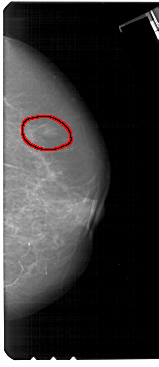

A_1357_1.RIGHT_MLO

RIGHT_MLO LINES 5491 PIXELS_PER_LINE 3226 BITS_PER_PIXEL 12 RESOLUTION 43.5 OVERLAY

FILE: A_1357_1.RIGHT_MLO.OVERLAY

TOTAL_ABNORMALITIES 1

ABNORMALITY 1

LESION_TYPE MASS SHAPE OVAL MARGINS ILL_DEFINED

ASSESSMENT 4

SUBTLETY 3

PATHOLOGY BENIGN

TOTAL_OUTLINES 1

BOUNDARY